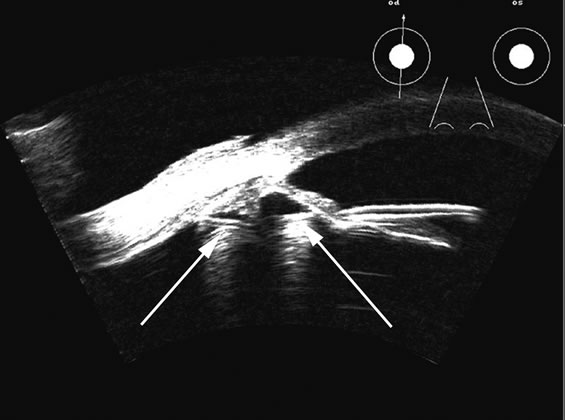

Fig. 17. This patient with a Molteno tube was treated for glaucoma. The top 50 MHz B-scan clearly shows the Molteno Tube (arrow). The bottom 10 MHz B-scan of the same patient demonstrates a choroidal detachment (large arrow) with associated posterior retinal detachment (small arrow). Choroidal elevations are typically convex, highly reflective surfaces with posterior limitation at the vortex vessels. Retina will always attach at the optic nerve. Choroidal elevations are often noted in several quadrants, as seen here.